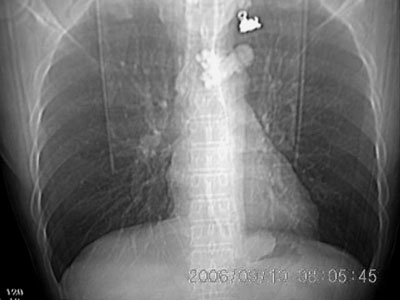

男 43 岁 左侧肩背部疼痛不适一个月,无畏寒 发烧 咳嗽.

左侧脊柱旁沟可见一边界清,密度不均匀之块状影,其内可见水样低密度影。

2、病变位于左肺下叶后段,周围肺组织相对干净,没有明显异常的改变,基本可以排除炎性病变;病变实质内密度均匀,边缘清晰,后下缘与膈脚分界不清晰。各征象均支持肺隔离症。

左下叶后基底段内胸主动脉旁可见一类梭形团块状影,边界较清楚,其内有小结节样高密度钙化影,肿块与胸主动脉可见条状影相连(见下图).

左肺下野后侧基底段见结节状肿块影,边界清晰锐利,其内见低密度坏死灶,紧贴胸膜生长,深分叶征不明显,纵隔内无明显肿大淋巴结,临床无咯血病史,所有征像均不支持恶性病变。病变考虑为纵隔内病变,没有增强扫描,定性很困难。